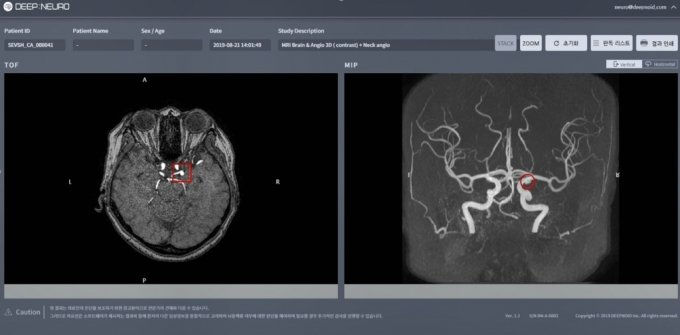

딥노이드는 뇌동맥류 AI(인공지능) 진단 소프트웨어 '딥뉴로'(DEEP:NEURO-CA-01)가 식품의약품안전처(식약처)로부터 2등급 의료기기 품목허가를 받았다고 24일 밝혔다.

딥노이드의 딥뉴로는 뇌혈관 질환 AI 기반 의료기기 소프트웨어다. AI를 활용해 뇌 MRI(자기공명영상장치) 영상에서 뇌동맥류로 의심되는 부위를 자동으로 검출해 의사가 보다 빠르고 정확하게 진단하도록 돕는 역할을 한다.